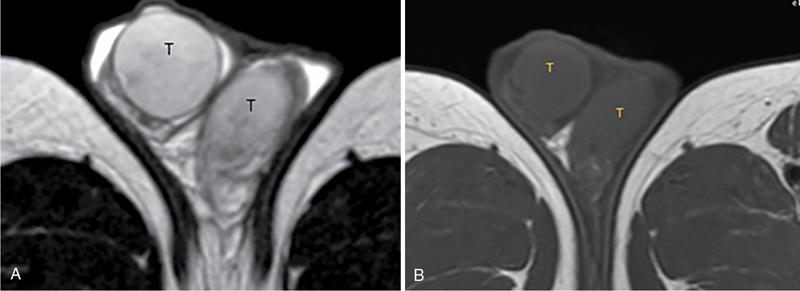

IMAGING ANATOMY OF MALE REPRODUCTIVE SYSTEM Ganesh Rajagopal The male reproductive system is formed by testes, ejaculatory ducts, seminal vesicles (SVs), prostate and penis. Various diagnostic imaging modalities like ultrasound (US), computed tomography (CT), magnetic resonance imaging (MRI) and positron emission tomography (PET) are helpful in the diagnostic evaluation of male reproductive system. Various indications for imaging may include acute scrotum (testicular torsion, trauma and epididymo-orchitis), scrotal swelling (hydrocele, spermatocele, idiopathic scrotal wall oedema and scrotal abscess) and infertility. US and MRI are the commonly used imaging modalities in male reproductive system which complement each other. CT is not very useful due to poor contrast resolution. Ultrasound imaging (US) with a high-frequency linear (7.5–10 MHz) transducer probe has become the imaging modality of choice for scrotal evaluation. Scrotal US is an excellent imaging modality as it can demonstrate abnormalities in testis as well as in paratesticular structures. Scrotal wall is formed by the skin, superficial fascia, dartos muscle, the external spermatic fascia, cremasteric fascia and the internal spermatic fascia. The scrotum is divided into two cavities by a median raphe. This multilayered scrotal wall is poorly delineated in US and MRI, it is typically hypointense on both T1- and T2-weighted images. Testes are paired organs, located normally in scrotal sac, suspended by the spermatic cords. Each testis is examined in orthogonal transverse and longitudinal planes, with both grey scale and colour Doppler modes, to assess its volume and blood flow. Volume of testis is calculated by length × height × width × 0.71. A total volume (both testes) of >30 mL and a single testicular volume of 12–15 mL is generally considered normal for adults. Testes are supplied by the testicular arteries, which arise from the aorta and enter the spermatic cord at deep inguinal ring to reach the upper pole of testis. Pampiniform plexus of veins surrounds the testis and appears as a serpiginous tubular structure posterior to it, measuring >2–3 mm in diameter. Testes are oval shaped, with homogeneous echotexture on grey scale US. Along with the epididymis, they are surrounded by an echogenic capsule, known as the tunica albuginea. Tunica albuginea is covered by tunica vaginalis, which is a remnant of the processus vaginalis and both represent closed sac of peritoneum with two layers. This tunica albuginea is seen extending into posteromedial testis and form the mediastinum testis (Fig. 11.2.1.1), which consists of ducts, nerves and blood vessels. The mediastinum testis is seen as a thin echogenic band. Rete testis is formed by the convergence of seminiferous tubules, seen as a hypoechoic area adjacent to mediastinum testes. The epididymis is a comma-shaped, elongated structure placed at the posterior border of the testis, which drains the efferent ductules (Fig. 11.2.1.2). It has head, body and tail. The head overlies the superior pole of the testis and is isoechoic or slightly hyperechoic whereas, the body and tail are located behind and along the inferior pole and are usually isoechoic. The tail of the epididymis continues into vas deferens (VD), which along with the nerves, lymphatic and vascular structures, forms the spermatic cord (Fig. 11.2.1.3). The spermatic cord appears as an echogenic band in the inguinal canal. The normal adult testis is a homogeneous oval structure that appears hyperintense on T2-weighted sequences and hypointense–isointense on T1-weighted images (Fig. 11.2.1.4). The tunica which surrounds the testis is hypointense T1- and T2-weighted sequences. Epididymis is isointense on T1-weighted images but hypointense on T2-weighted images compared to testis (Fig. 11.2.1.5). Both testicles and epididymis enhance after intravenous administration of gadolinium (Gd) MR contrast agents. Prostate, though visualized by transabdominal scan is better assessed by transrectal high frequency (7.5–10 MHz) ultrasound transducer (TRUS) with patient in left lateral decubitus position. The prostate gland is divided into the anterior fibromuscular stroma (devoid of glandular tissue), transition zone, central zone, periurethral zone and peripheral zone. The base of the prostate is located superiorly and contiguous with the bladder neck whereas, the apex of the prostate is located at the inferior aspect continuous with the striated muscles of the urethral sphincter. The neurovascular bundle is seen to course near the posterolateral aspect of prostate, which is a preferential route of tumour spread. The prostate appears as a cone-shaped organ and shows uniform low echogenicity (Fig. 11.2.1.6). The outer gland (central and peripheral zones) is generally more echogenic than the inner gland. The transition and central zones of the prostate have similar MR signal intensity and cannot be differentiated, hence, are collectively referred as the central gland. On T2-weighted MR images, the normal peripheral zone is homogeneously hyperintense, whereas the central gland tissue is typically hypointense or isointense compared to the skeletal muscle (Fig. 11.2.1.7). The capsule and the anterior fibromuscular stroma appear hypointense on T2-weighted MR images. The SVs are seen as septate tubular cystic structures, appearing uniformly anechoic in US, above the prostate with distal portion of VD is seen medial to it. The duct of SV and VD joins to form the ejaculatory duct, which drains into the prostatic urethra via verumontanum. SVs show ‘bow-tie’ appearance in transversal scans, and a club or tennis-racket shape in longitudinal scans (Fig. 11.2.1.8). On MR, SVs are seen as elongated fluid-containing structures with thin septa, which is hypointense on T1 and hyperintense on T2-weighted MR images (Fig. 11.2.1.9). The VD is seen as a tubular structure with low signal intensity in both T1- and T2-weighted images, on either side. The dilated distal portion of VD (ampulla), appears hyperintense on T2-weighted images, similar to that of the SV due to the fluid content (Fig. 11.2.1.10). The penis, being a superficial organ, is usually examined with US, although MRI is reserved as problem solving modality. The penile body contains two paired muscles – corpora cavernosa and a corpus spongiosum. The former performs as a main erectile body while the latter contains the penile urethra (Fig. 11.2.1.11). Dartos fascia forms the outer layer and the Buck fascia forms the inner layer, which contain the deep dorsal vein (DDV) and a paired dorsal neurovascular bundle. The corpus spongiosum and corpora cavernosa are of high signal intensities on T2-weighted MR images and intermediate-low signals on T1-weighted MR images. The tunica albuginea being a fibrous sheath, surrounds all the three muscles, is hypointense on all sequences (Fig. 11.2.1.12). IMAGING ANATOMY OF FEMALE REPRODUCTIVE SYSTEM Saranya The female reproductive system comprises of uterus, cervix, fallopian tubes, ovaries, vagina and vulva. Ultrasonography (transabdominal and transvaginal) is the primary imaging modality of choice for imaging the female pelvis. Computed tomography (CT) is less often used for pelvic imaging. It provides a quick and systematic overview with coverage of the abdomen in the same session. Hence, CT is well suited for staging pelvic cancers and for imaging gynaecologic and nongynaecologic diseases presenting with acute abdominal pain. Pelvic anatomy is well demonstrated by magnetic resonance imaging (MRI). The contrast resolution of T2-weighted images form the basis for superb tissue characterization of MRI. Uterus is a thick-walled fibromuscular organ composed of myometrium and endometrium. It has two major divisions, namely, the body (corpus) and cervix. The fundus lies above the ostia of fallopian tubes. The normal uterus measures between 5 and 9 cm in length and is in an anteverted position, in relation to the urinary bladder. The myometrium shows three layers on USG, a compacted thin, hypoechoic inner layer forms subendometrial halo, a thicker, homogenously echogenic middle layer and a thinner, hypoechoic outer layer (peripheral to arcuate vessels). The appearance of the endometrium varies with the phase of the menstrual cycle. It appears as a thin echogenic line early in the proliferative phase and shows hypoechoic thickening (4–8 mm) as proliferative phase progresses. It shows a triple layer (sandwich or trilaminar) appearance in the mid cycle and may measure up to 12–16 mm. During secretory phase after ovulation, the layers are seen hyperechoic due to the increasing complexity of glandular structure and secretions (Fig. 11.2.2.1). Postmenopausally, the endometrium decreases in thickness. Endometrial thickness of 5 mm is taken as cut-off. Women on hormonal therapy acceptable endometrial thickness is up to 8 mm. Three-dimensional US permits multiple views to be reconstructed from a single sweep through the uterus. Sonohysterogram is the study of choice for detailed evaluation of the endometrial cavity pathologies. The cervix begins at the inferior narrowing of the uterus (isthmus) at the internal os, which is identified by the entrance of uterine vessels. It has supravaginal and vaginal portions. It is 3–4 cm long and shortens after childbirth. In premenarche women, cervix is larger than corpus, forming approximately 2/3 of the uterine mass. During menarche, there is preferential growth of the corpus and in nulliparous women, corpus and cervix are roughly equal, whereas in parous woman, corpus forms approximately 2/3 of the uterine mass. Uterus is an extraperitoneal organ. The peritoneum extends over urinary bladder dome to anterior uterus, forming anterior cul-de-sac (vesicouterine pouch) and posteriorly, the peritoneum extends more inferiorly to the upper portion of vagina, forming the posterior cul-de-sac (pouch of Douglas, rectouterine pouch), which forms the most dependent portion of the female pelvis. Supporting ligaments of the uterus comprise mainly of broad ligaments, which extend laterally to the pelvic wall and round ligaments, which arise from uterine cornu near fallopian tubes to course anteriorly, pass through the inguinal canal to insert on the labia majora. Connective tissue thickening at the base of the broad ligament forms the uterosacral ligaments posteriorly, cardinal ligaments laterally and vesicouterine ligaments anteriorly. CT examination displays the uterus as a triangular or ovoid soft tissue structure behind the urinary bladder (Fig. 11.2.2.2). Following the administration of intravenous contrast, there is enhancement of myometrium that helps to delineate the endometrium. The vagina, cervix and corpus can be differentiated by morphological characteristics and enhancement pattern. The uterine corpus is typically triangular, whereas cervix is more rounded. The vagina has an appearance of flat rectangle at the level of fornix. The broad ligament and round ligaments are seen coursing laterally and anteriorly, respectively. The main source of vascular supply to uterus is from the uterine arteries. The uterine arteries pass within the broad ligament to enter the uterus, adjacent to the lateral fornices. The uterine artery passes over the ureter at the level of the cervix. Then it courses superiorly, along the lateral margin of the uterus and anastomoses with the ovarian artery. Uterine arteries give rise to arcuate arteries, which run in the outer third of myometrium. Radial arteries extend through the myometrium, which terminate as spiral arteries in the endometrium. The venous system parallels the arterial system, forms a complex venous network in the parametrium and drains to the iliac veins. Middle and lower thirds of the uterus are drained by obturator, parametrial and paracervical lymph nodes. Lymphatic drainage from the upper corpus and fundus goes to the common iliac and paraaortic lymph nodes. MRI provides a more comprehensive view of the uterine anatomy. On MRI, the uterus and cervix show uniform low to intermediate signal on T1-weighted images. On T2-weighted images, uterus shows three distinct zones, namely high signal endometrium, low signal junctional zone and intermediate signal myometrium (Fig. 11.2.2.3). The normal thickness of the junctional zone varies from 2 to 8 mm. A thickness of 9 to 12 mm is equivocal and greater than 12 mm is abnormal. Both endometrium and junctional zone become thin with oral contraceptive intake. Endometrial atrophies and the junctional zone is absent in postmenopausal women. The endocervical canal shows high signal on T2-weighted images, whereas cervical stroma shows low signal, contiguous with the junctional zone. An outer layer of intermediate signal smooth muscle is present. Nabothian cysts representing obstructed, mucous secreting glands are commonly seen as low signal on T1-weighted images and high signal on T2-weighted images. Parametrium shows low to intermediate signal intensity on T1-weighted images and variable signal intensity on T2-weighted images. The round ligaments and uterosacral ligaments show low signal intensity, cardinal ligaments and associated venous plexuses show high signal intensity on T2-weighted images. Ovaries are located posterolateral to the body of the uterus between the uterus and the pelvic sidewall. The internal iliac vessels lie immediately posterior to the ovary. Exact position is variable due to the laxity in the ligaments, parity, uterine size and position. On USG, medulla of the ovaries is mildly hyperechoic compared to the hypoechoic cortex. Developing follicles appear anechoic (Fig. 11.2.2.4). Corpus luteum may have a thick, echogenic ring and haemorrhage is common.